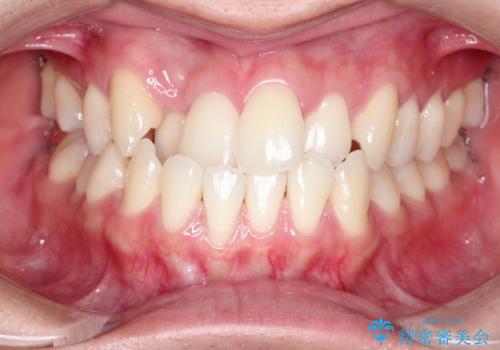

八重歯とクロスバイト 目立たないワイヤー装置での抜歯矯正